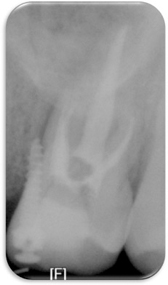

Figure 2

Pre-operative periapical x-ray.